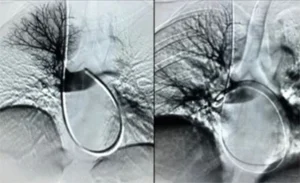

Embolia polmonare submassiva: riguarda trombi di dimensioni intermedie che ostruiscono rami arteriosi più periferici, provocando una manifestazione meno grave rispetto alla forma massiva.

Embolia polmonare asintomatica: si verifica quando il trombo è di piccole dimensioni e occlude solo piccole ramificazioni periferiche. Sebbene spesso asintomatica, nel tempo può causare ipertensione polmonare.